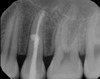

Vertical marginal bone loss adjacent to root – diagnosis?

A

• Periodontitis marginalis chronica

• (chronic marginal periodontitis).

• Treatment: Periodontal therapy or extraction

* Periodontitis marginalis chronica * (Chronic marginal periodontitis) → Vertical/angular bone loss